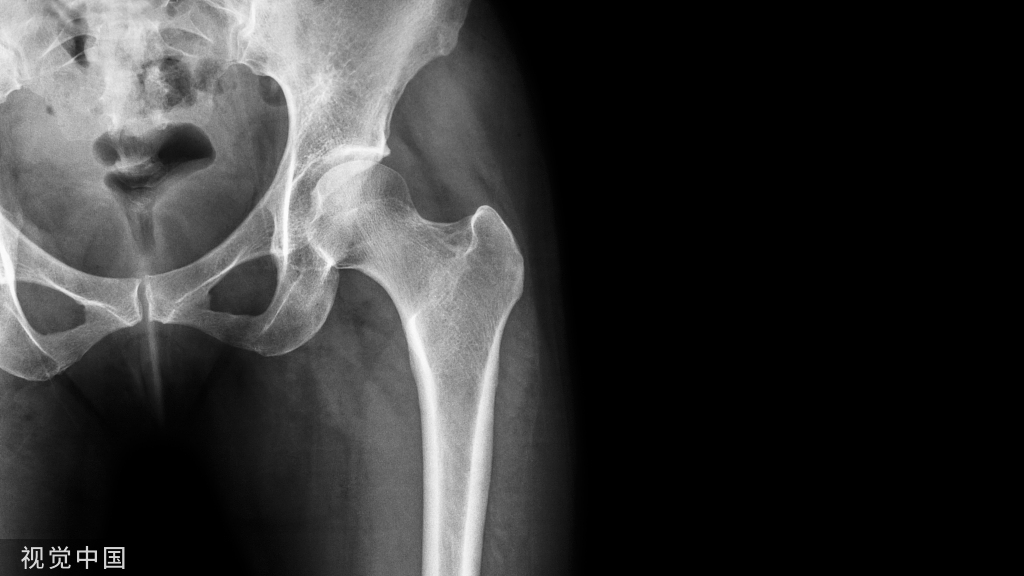

由于桡骨头为肘关节的稳定提供了重要的前方和外翻支撑作用,因此不能轻易切除。临床上根据术中情况进行固定或置换(图3,桡骨头的固定或置换)。当桡骨头损伤<25%时,因骨折块太小或合并骨质疏松不宜采取内固定,可考虑切除桡骨头骨折块。在切除桡骨头骨折块后,通常需评估肘关节的稳定性。若持续存在肘关节不稳定,则考虑行桡骨头置换术。若桡骨头骨折可修复,则在解剖复位后用较小的埋头螺钉或钢板进行固定,建议采用埋头螺钉固定。若桡骨头和桡骨颈广泛粉碎或骨质很差,则需考虑行人工桡骨头置换术。目前,临床上有多种可用的假体,但通常建议使用组配型假体,术者可根据个体解剖差异确定人工桡骨头的大小及假体柄的直径和高度,以获得最佳的治疗效果。需要明确的是应根据切除的桡骨头来选择桡骨头假体的大小,假体的高度也应与切除骨块的高度一致,以免置入的桡骨头假体过高。“过度填塞”是人工桡骨头置换最常见的并发症,即假体位置过高或假体直径过大,可导致肘关节及前臂活动受限,未达到桡骨头置换的目的。